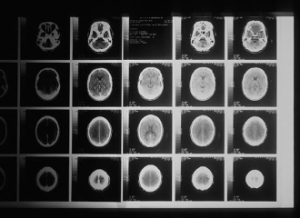

在小鼠气道中的核心蛋白聚糖是一个麻烦。它会作用于气道的组织,加重哮喘的症状。但是Chatterjee和Gutmann发现在大脑中的核心蛋白聚糖是有益的。大脑中的核心蛋白聚糖能作用于小胶质免疫细胞,通过干扰炎性转录因子NFkappaB的激活通路阻止小胶质细胞的活化。激活的小胶质细胞会促进大脑肿瘤的生长和进展。

使用核心蛋白聚糖或能抑制NFkappaB激活通路的咖啡酸苯乙酯(caffeic acid phenethyl ester,CAPE)进行治疗能够防止带有NF1突变基因的小鼠患视神经胶质瘤。研究发现,阻断小胶质细胞的激活可能是治疗大脑肿瘤的有效方法。

遗传学、神经外科学与儿科学教授Gutmann说:“研究最激动人心的部分在于,它表明体内T细胞和大脑内与视神经胶质瘤形成与生长有关的细胞存在正常的交流。我们的下一步是研究这种联系是否也适用于其他类型的大脑肿瘤。我们还将研究湿疹和幼儿感染的作用,因为这些疾病也都涉及T细胞。既然我们已经了解到T细胞和促进大脑肿瘤生长的细胞之间存在联系,我们将开始寻找介入这一过程的有效疗法。”